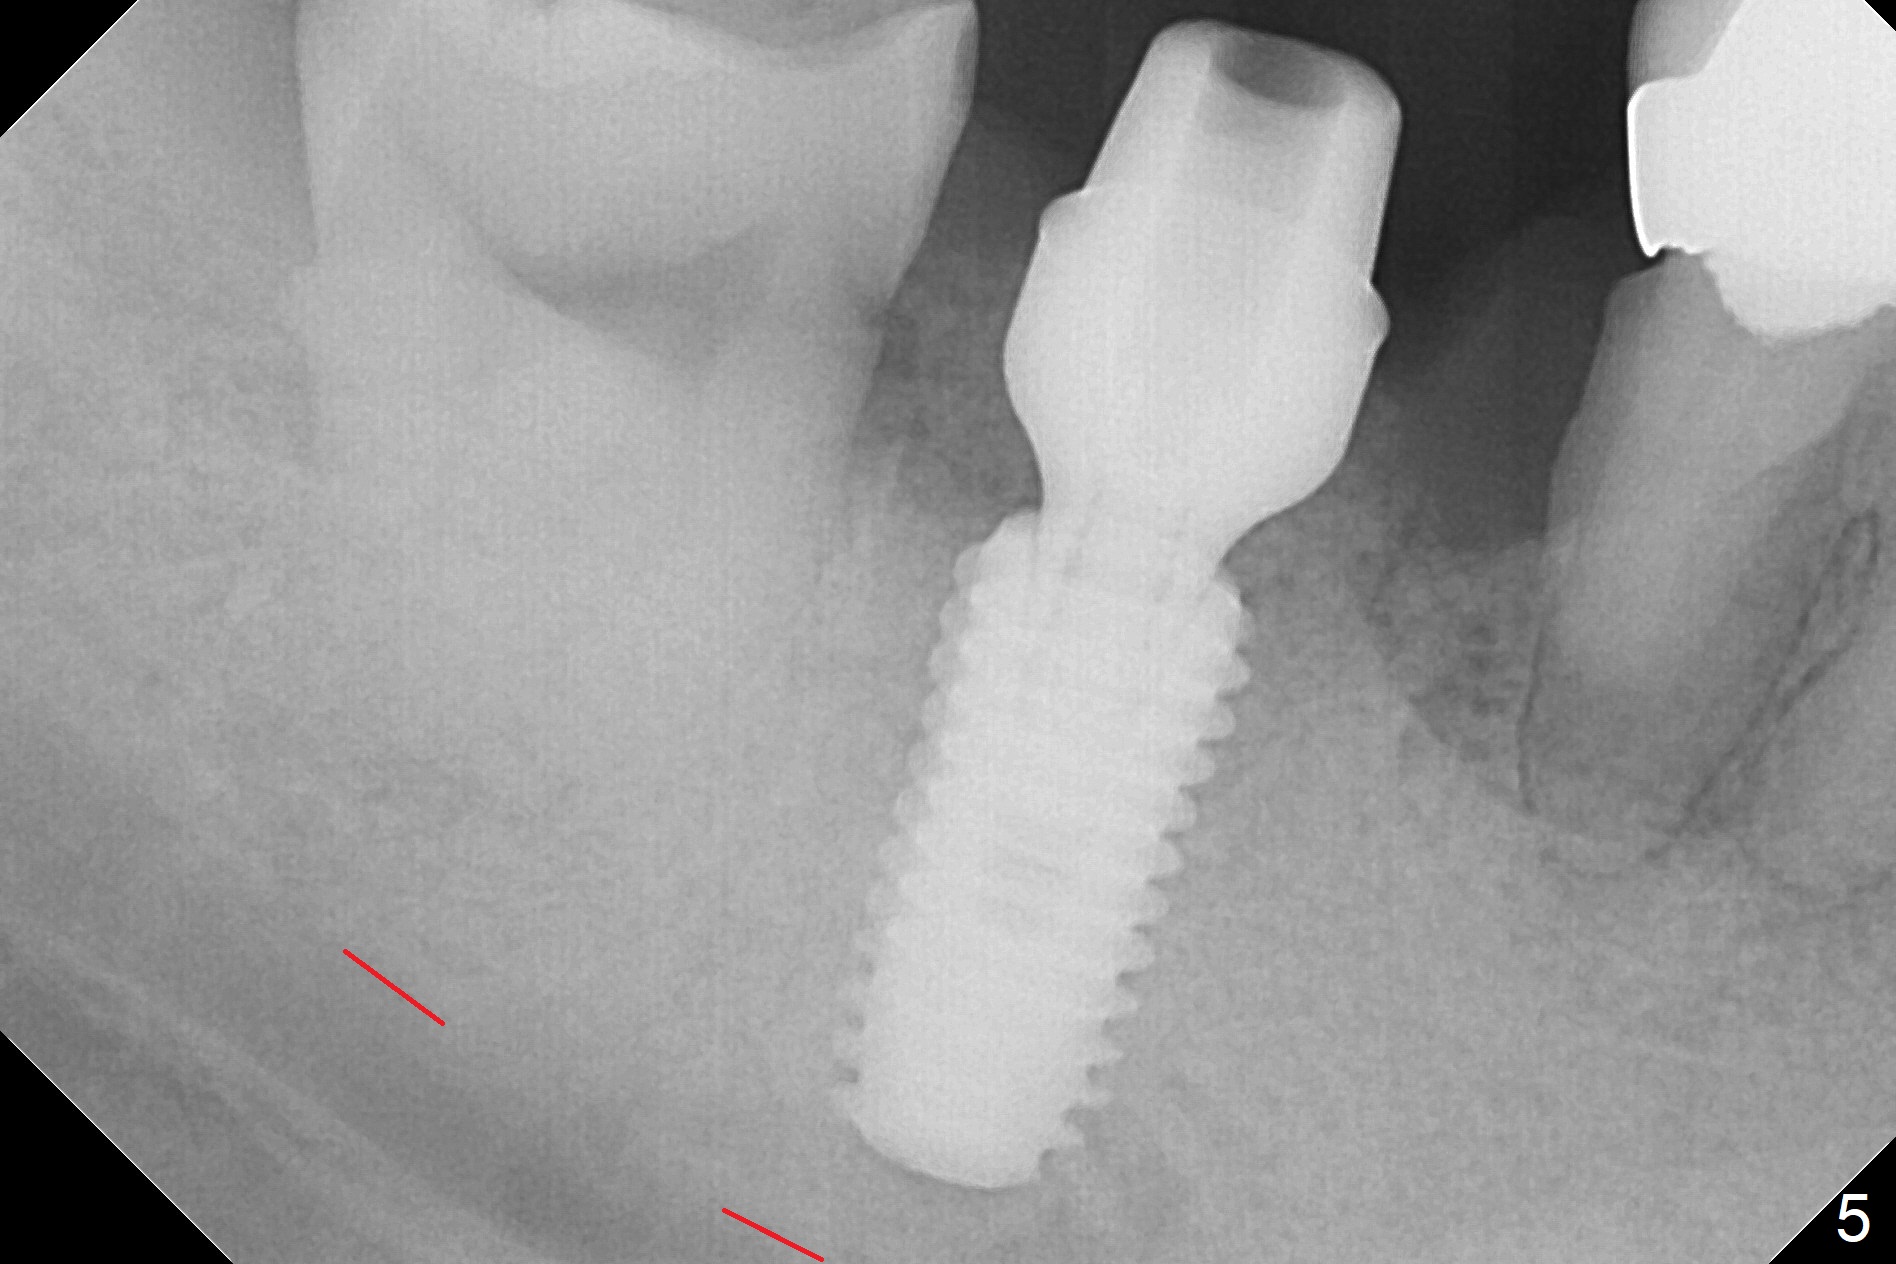

Although the tooth #30 has distobuccal root exposure (Fig.1 <), it is asymptomatic.  In contrast the tooth #31 with the distoocclusal caries (*) is symptomatic.  After use of 2 mm drill for 18 mm (lingual gingival margin), a calculated parallel pin is inserted (Fig.2 (D: 2 distal roots of the tooth #30)).  It appears that a 11.5 mm long implant is appropriate for the site; a 5 mm cuff is expected.  Following 4.8 mm drill, a 5.5x11.5 mm implant is placed initially (Fig.3) with an apical space (*) and clearance from the Inferior Alveolar Canal (red dashed line).  The implant is placed deeper with placement of a 6.5x4(5) mm abutment and bone graft (*, Fig.4,5).  After placement of collagen membrane over the graft, an immediate provisional is fabricated (Fig.6 P) with clearance from the opposing tooth (Fig.7 *).  There is no bone loss 3.5 months postop (Fig.8).  In fact the abutment has not been seated completely since its placement (Fig.4,5,8).  The crown/abutment dislodges 3 years 3 months post cementation (Fig.9).  The latter occurs for long incubation time because of opposing partial denture (Fig.10).  After trimming proximal surfaces (Fig.11: arrowheads), the abutment remains incompletely seated (Fig.11) due to possible crestal bone interference (Fig.11 *).  The smaller abutment by itself remains unseated (Fgi.12).  One size small one is completely seated (Fig.13).  Impression is taken.  Two weeks later the abutment margin is supragingival.  After screw torque at 20 Ncm, the crown is cemented with access hole.  Excess cement is removed.